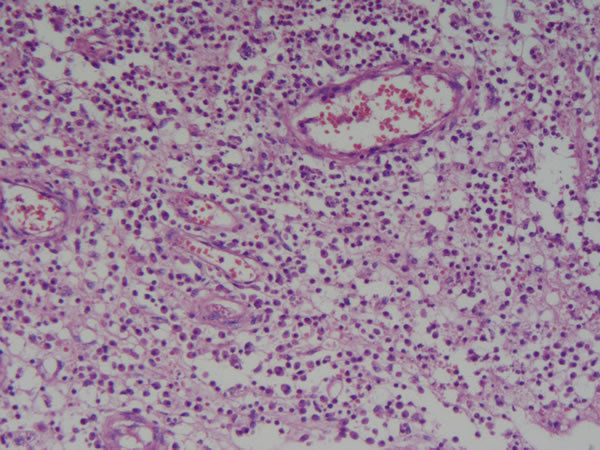

Iaapend1 (image/jpeg)

Apêndice cecal normal |

Image:

Iaapend3 (image/jpeg)

Apêndice cecal - Epitélio cilíndrico simples, tec. conjuntivo e muscular liso. Infl. aguda - apendicite aguda Mucosa preservada e luz do órgão preenchida por exsudado fibrino-leucocitário com hemorragia Causas: infec. necrose, reação imune |